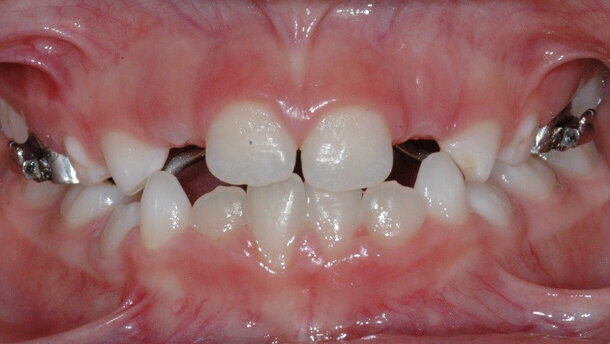

Vista frontale di inizio caso.